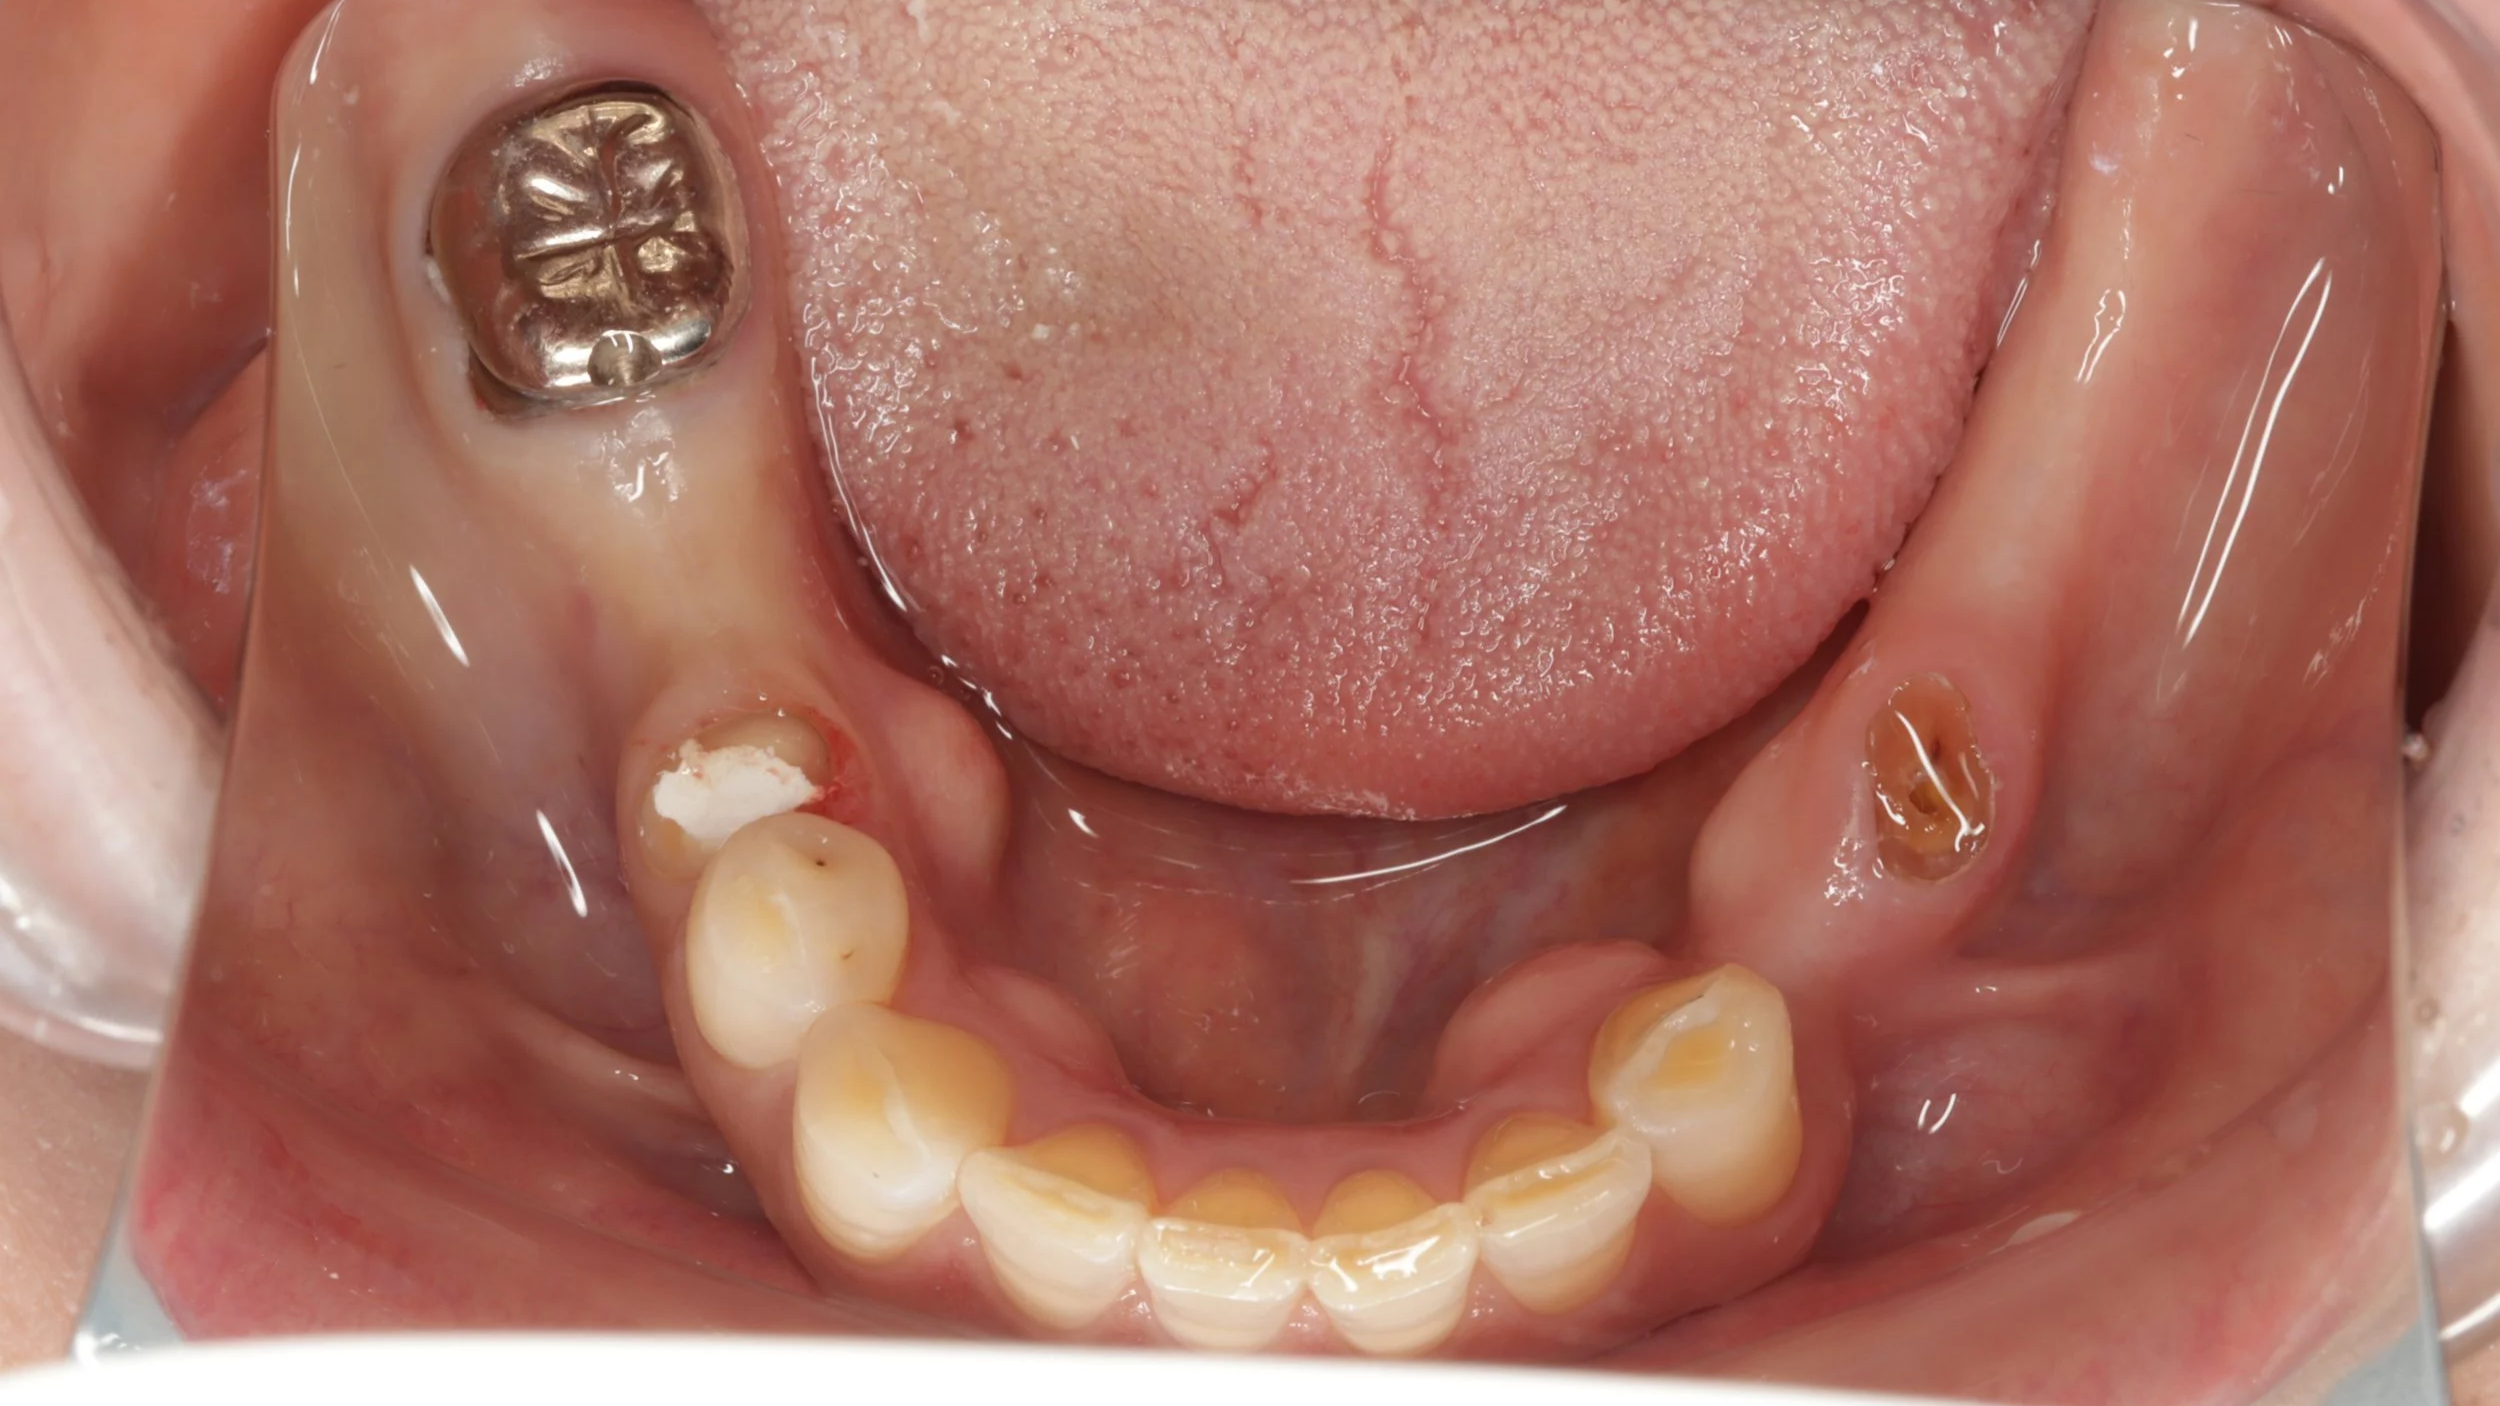

初診時

大きなむし歯もある状態でしたがまずは、入れ歯を早期に装着し、入れ歯の調整をしつつ、歯の治療することとしました。

2回目

残せる歯は、しっかり根の治療を開始しつつ、新しい入れ歯を装着。内側を金属で薄く作る事で違和感の軽減を図りました。